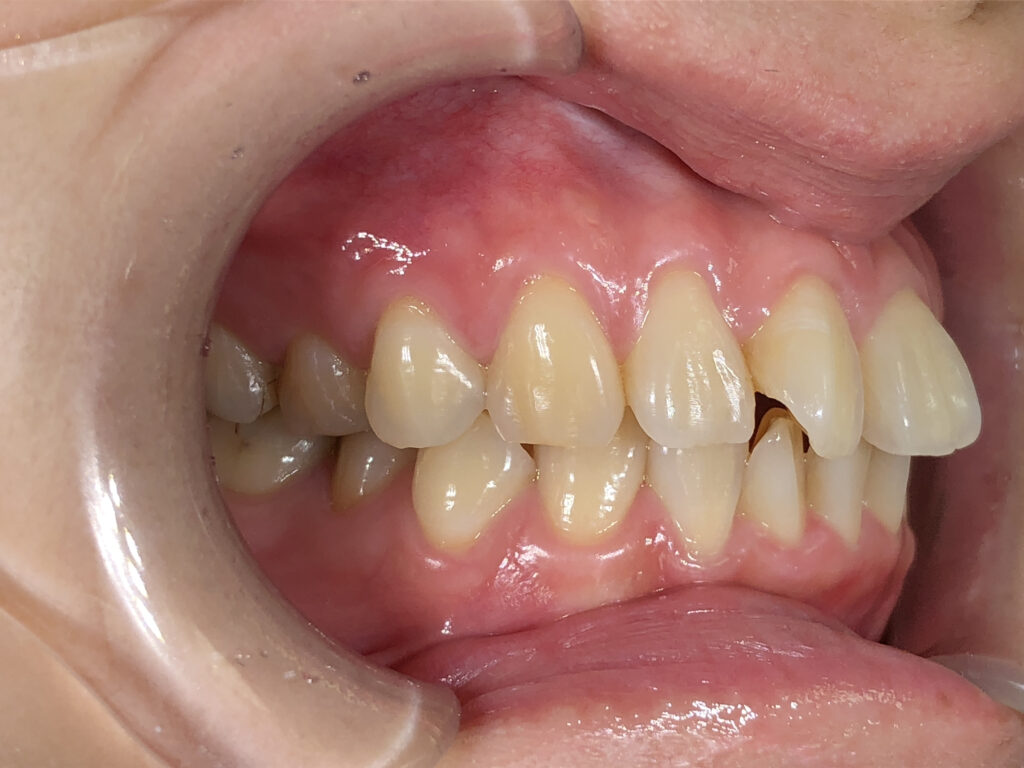

右側

治療前

治療後